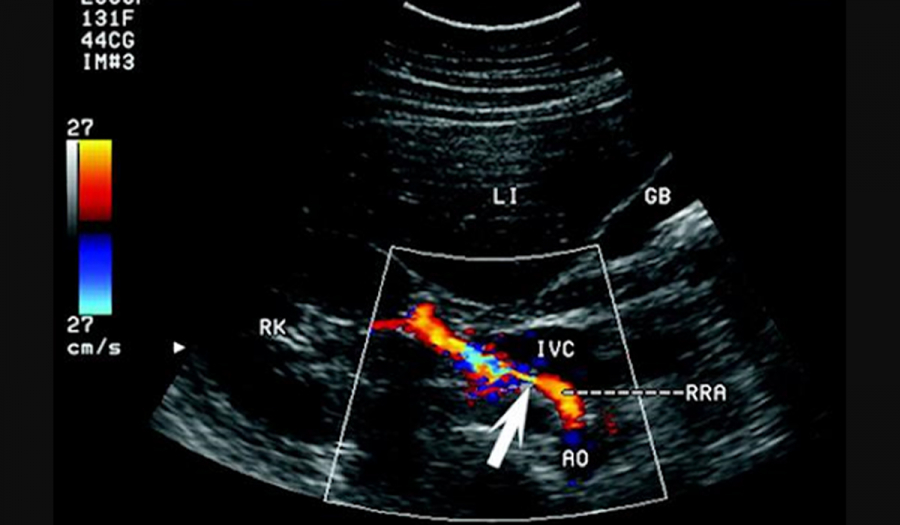

Дбаємо про здоров'я судин шиї та голови.

Показання: